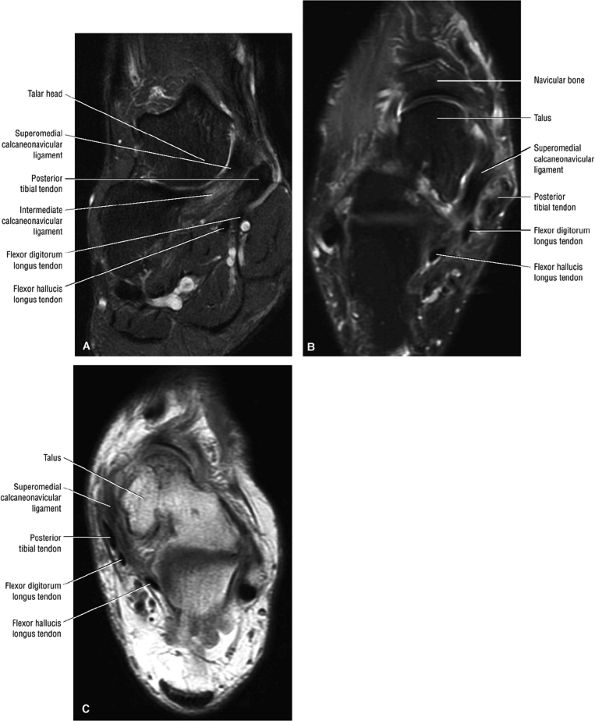

The spring ligament complex consists of three components: the lateral, intermediate, and superomedial oblique calcaneonavicular ligaments.

structures are critical static stabilizers of the medial longitudinal arch of the foot, providing support for the head of the talus at the talocalcaneonavicular joint (or acetabulum pedis). The other major stabilizer of the medial longitudinal arch, the PTT, is a dynamic stabilizer. Pathology of the spring ligament complex rarely occurs in isolation and is almost always associated with PTT dysfunction. Attention to the components of the spring ligament on routine MR imaging of the foot is important, since there is often a cascade of failures that can lead to or be seen with acquired pes planus deformity.